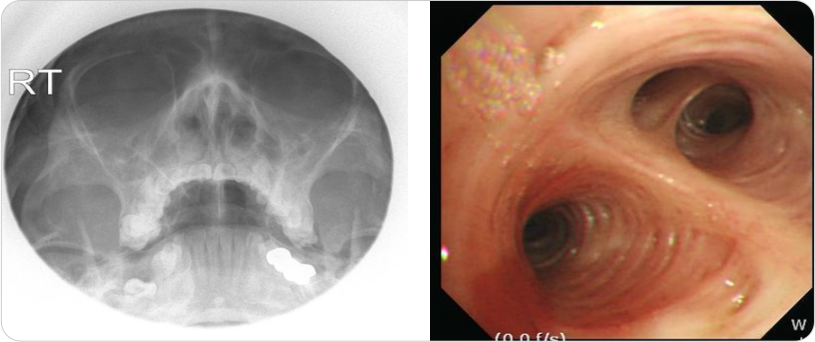

흉부 X선 검사 및 흉부 CT 검사에서는 폐의 침윤 소견 및 폐의 낭성 변화로 인한 기찻길 모양의 tram track sign 및

반지 모양의 signet ring sign을 확인할수 있습니다.

그림2 : 기관지확장증 환자의 흉부X선 (양쪽 폐중부 하부 침윤) 및 CT 사진(낭성 변화 및 tram track sign)

한편 동반되는 부비동염을 확인하기 위하여 부비동 X선 촬영을 하기도 하고, 동반되는 폐기능 감소를 확인하기 위해서

폐기능 검사를 시행하기도 하며, 감염 원인균 확인을 위해서 객담 배양 및 감수성 검사를 하고 객혈의 출혈 부위 확인을 위해서

기관지 내시경을 시행하기도 하며, 동반 질환의 진단을 위해서 혈액 검사 및 알러지 검사를 하기도 합니다.

그림3 : 기관지확장증의 부비동사진(양쪽 부비동염) 및 기관지내시경 사진(기관 내 염증 및 출현흔 확인)